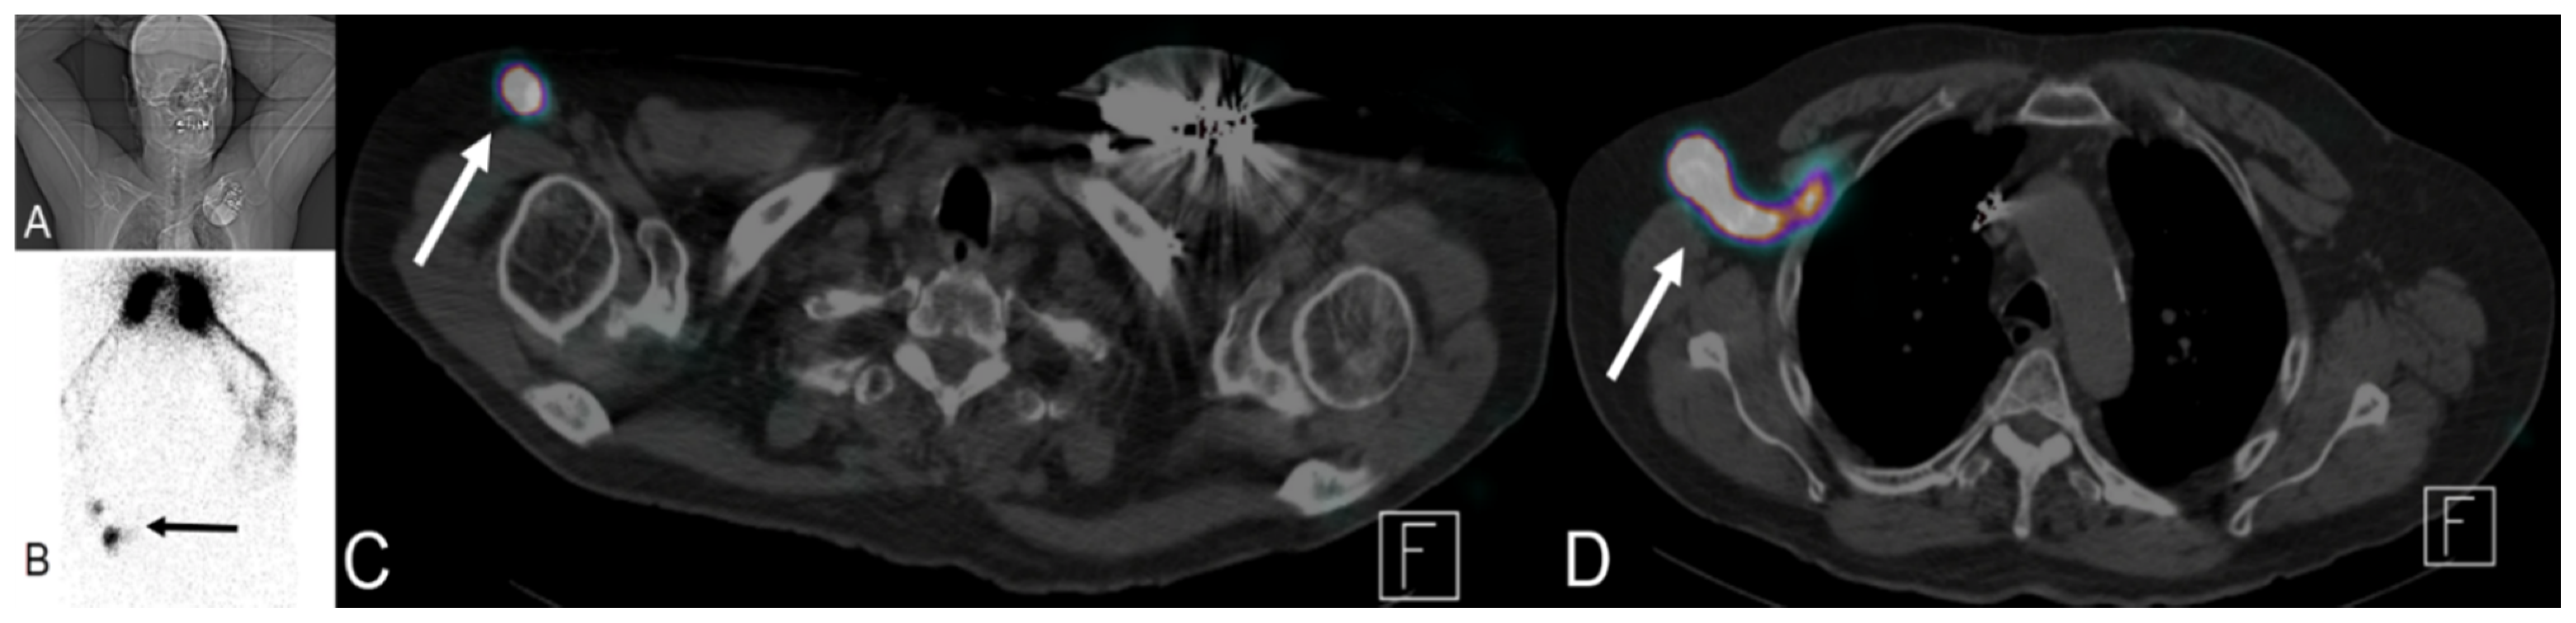

4.1.3. Positron Emission Tomography (PET) and Positron Emission Tomography-Computed Tomography (PET-CT)

4.3. Sentinel Lymph Node (SNL) Imaging

Lymphoscintigraphy